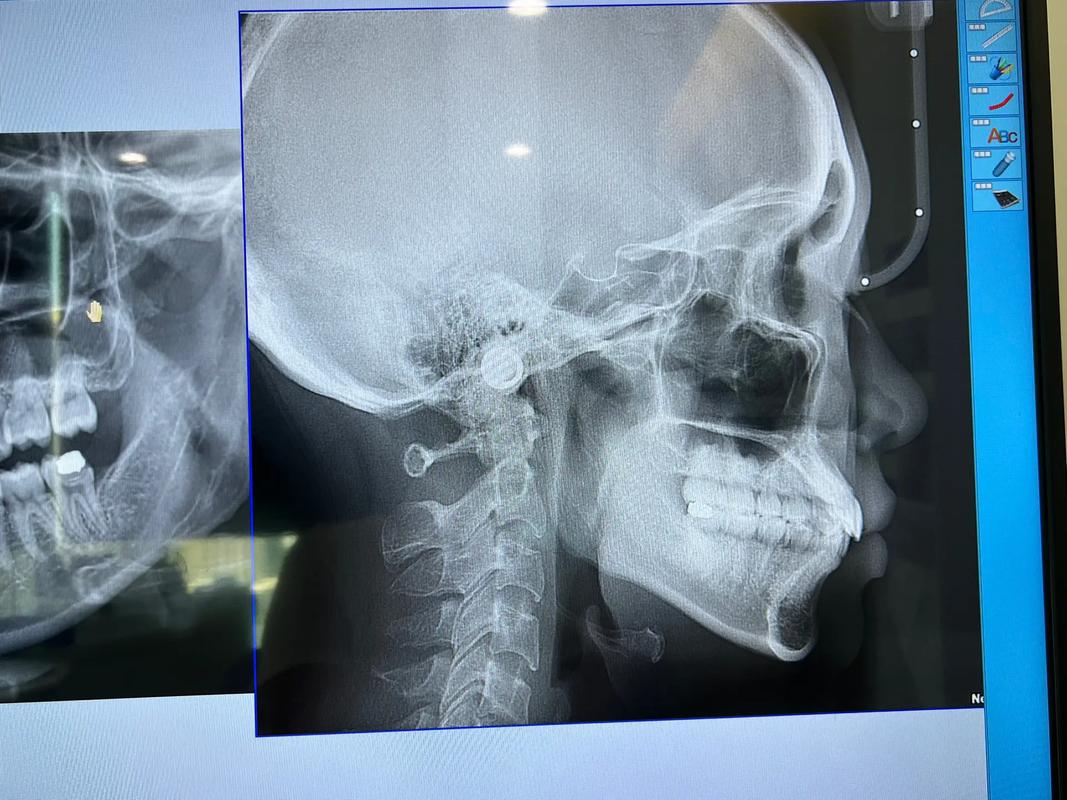

- 头颅侧位片:正畸诊断的“金标准”,用于测量骨骼关系(如SNA角、SNB角、ANB角判断上下颌位置)、牙齿倾斜度(UI-SN、LI-MP等)、软组织轮廓(鼻唇角、颏部突度),需在严格头位下拍摄(法兰克福平面与地面平行),确保测量数据可靠。

| 头颅侧位片 | 骨骼关系、牙齿倾斜度 | 头位固定,放大率1:10 | 诊断骨性错𬌗,制定治疗方案 |